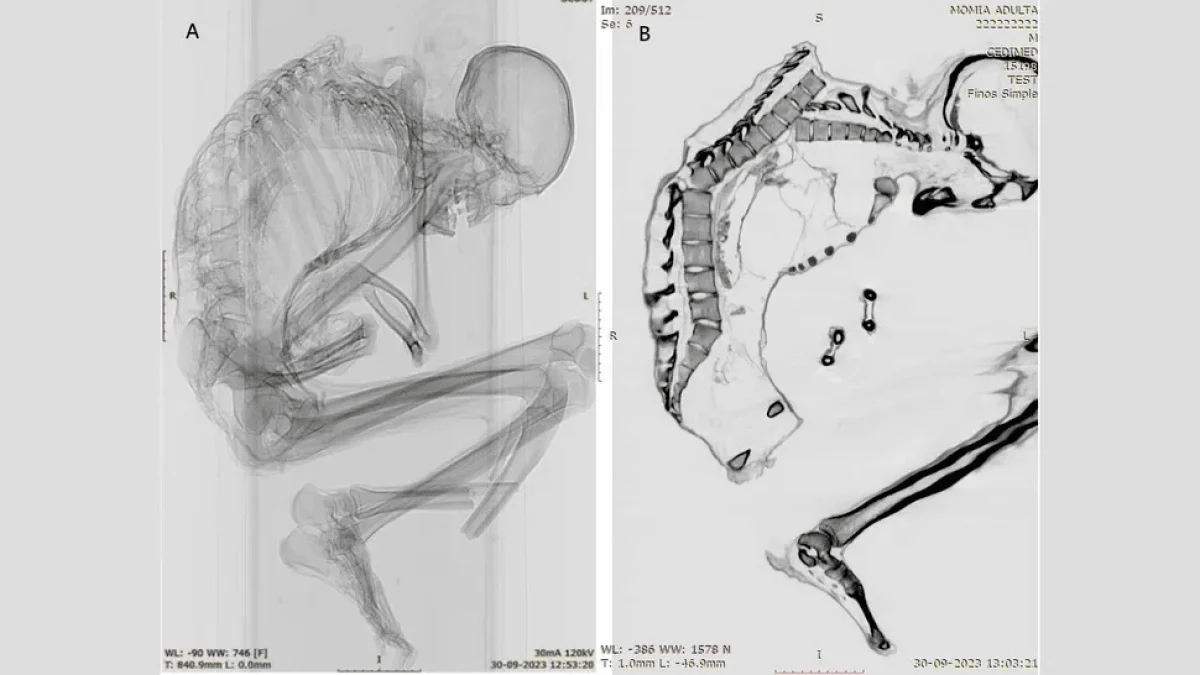

Каталіна Моралес і Франсіско Гаррідо, археологи з Національного музею природної історії в Сантьяго, використовували комп’ютерну томографію і рентгенівські знімки, щоб виявити найдрібніші деталі великої травми, яка, ймовірно, призвела до смерті чоловіка. Вони повідомили:

Травми, отримані чоловіком

За словами вчених, на верхній частині хребта чоловіка були виявлені численні незагоєні переломи. У нього також були переломи ребер, лопатки і ключиці, що вказує на “сильний удар по великій області” верхньої частини спини, показуючи, що “верхня ліва частина грудної клітки прийняла на себе основний удар”. Удар змістив кілька хребців і зруйнував грудну клітку.

Крім того, дослідники виявили перелом біля основи хребта, який був результатом первинної травми верхньої частини спини. Вони написали:

Важливо, що на черепі, шиї та руках чоловіка не було виявлено жодних пошкоджень, що вказує на те, що удар стався, коли чоловік перебував у положенні головою вниз. Можливо, він активно займався видобутком корисних копалин або намагався захистити голову руками, коли на нього впав важкий предмет зверху. Подібні травми спостерігаються у людей, які постраждали від землетрусів, а також при виробничих травмах у лісовій, будівельній та гірничодобувній промисловості.